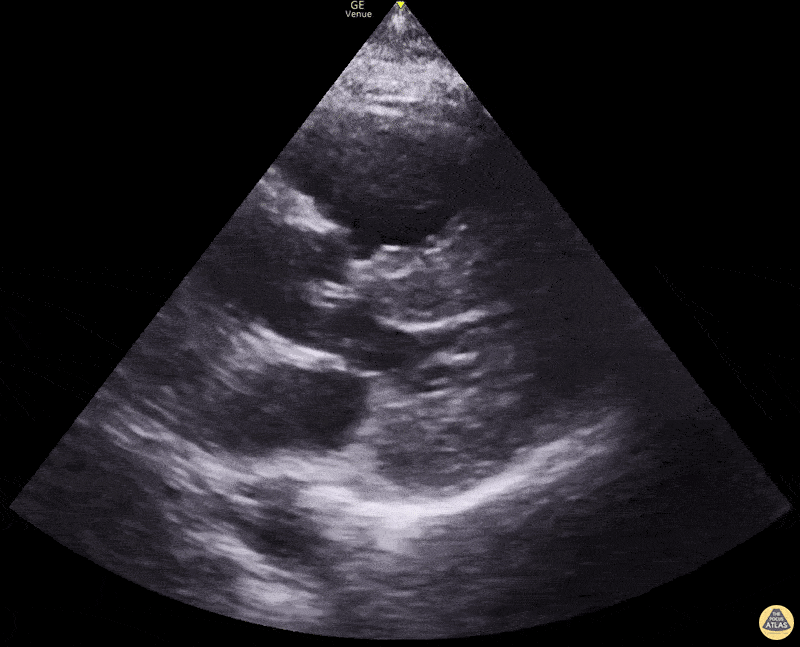

Right Ventricular Dysfunction - Right heart enlargement in PSLA

Right ventricular enlargement in parasternal long view. Using the normal 1:1:1 ratio of LV:LVOT:RV you can see that RV in this clip is larger than the LV and LVOT. Dimitri Livshits DO, Ultrasound Fellow; Jane Belyavskaya MD, Ultrasound Fellow; Chris Hanuscin MD, Ultrasound Division Director (Kings County/SUNY Downstate)